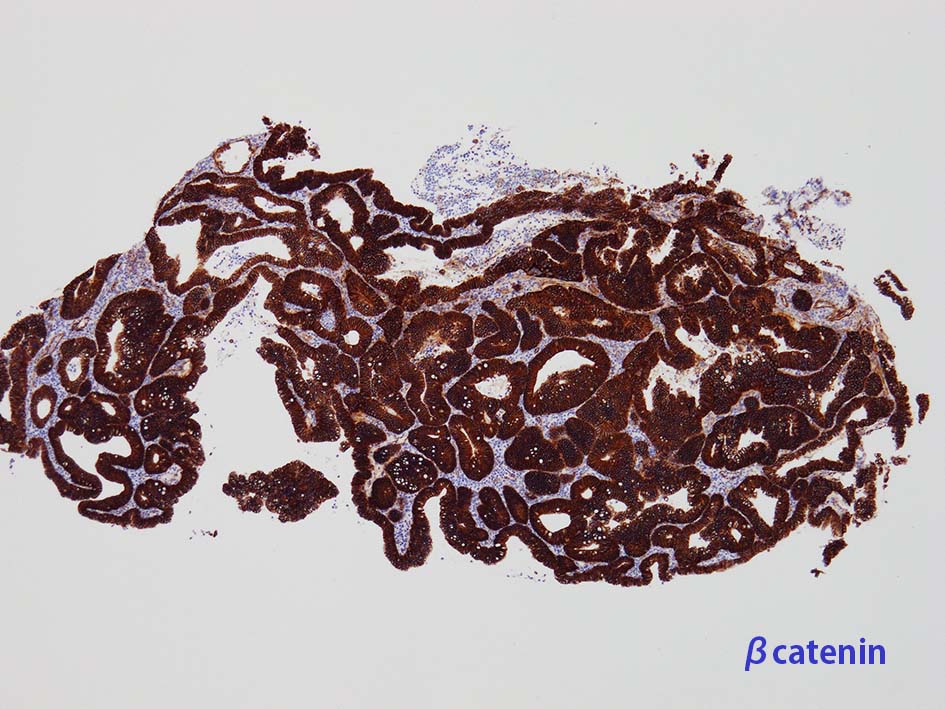

膀胱原発腺癌の診断に, サイトケラチン7および20、34βE12、トロンボモジュリン、CDX2およびβカテニンなどの免疫組織化学的パネルが提案されている。しかし他の原発部位に発生する腺癌と組織像だけでなく免疫組織化学的特徴が重複している. 原発性腺癌と転移性腺癌では予後や治療法が大きく異なるため, 鑑別診断において膀胱腺癌の診断を下す際には、臨床的、画像的、組織的、および免疫組織化学的な相関を注意深く確認する必要がある。

腸管型の腺癌。大腸の高分化腺癌と組織学的に区別は難しい.